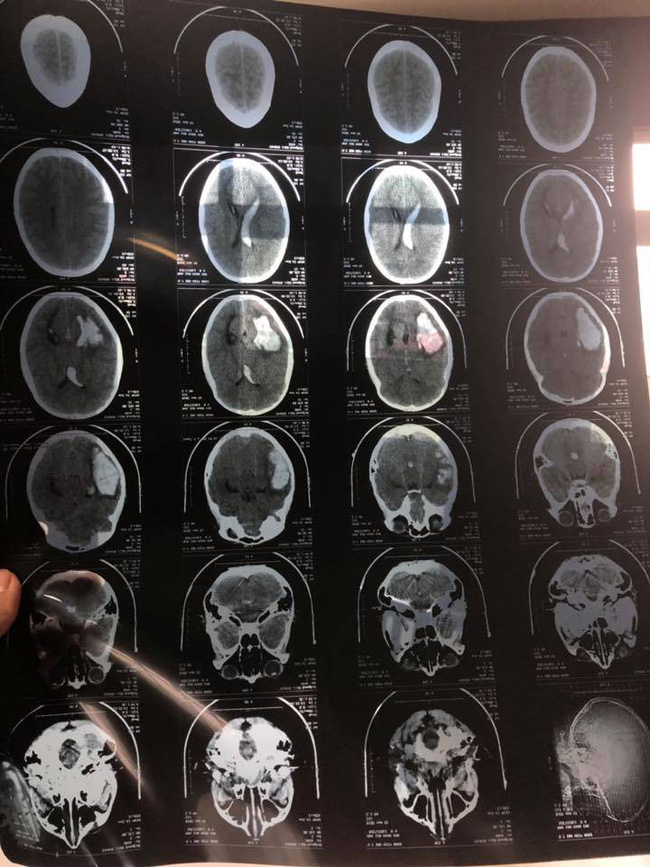

"Mình nhận được một lời khuyên nên chọc não úng thủy sớm để phát hiện ra bệnh sớm cho con và đã quyết định sẽ làm. Nhưng khi chuẩn bị chọc não úng thủy, đột nhiên bác sĩ điều trị nhận được chỉ định từ bác sĩ trưởng khoa cho đi chụp cắt lớp trước. Rồi con được xuống chụp cắt lớp, kết quả nhanh chóng được đưa ra. Bác sĩ chuyên khoa thông báo, con bị xuất huyết não nặng do dị tật ống thần kinh trong não tự vỡ. Trường hợp này phải phẫu thuật càng sớm càng tốt để hút máu não tụ ra. Còn dị tật kia nếu tìm được thì sẽ xử lý, còn nếu không phải đóng lại sau vài tháng ổn định sẽ tìm, mổ và cắt sau".

Kết quả chụp cắt lớp phát hiện xuất huyết não do dị tật mạch máu não tự vỡ.